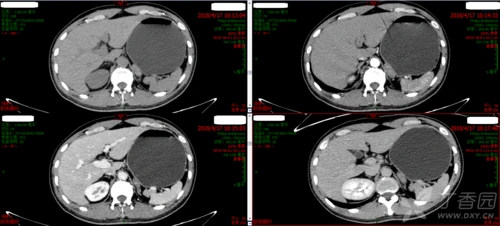

轴状面,冠状面,矢状面源图像和不同方法的融合图像